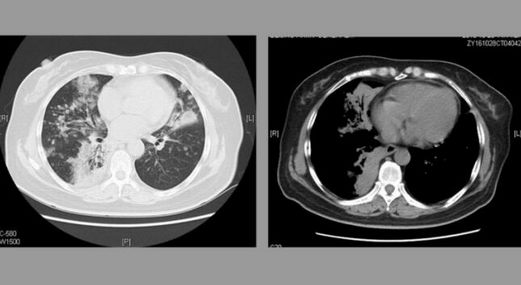

2019年3月份,家住肥西的刘大爷突然出现无故咳嗽,而且伴有痰血,随后到附近医院进行检查。DR检查报告单显示:刘大爷被确诊为肺癌。确诊后,医生建议其住院接受手术切除。

4月16日,由于未能得到及时、有效的治疗,复查结果显示团块状影已经长到70mm✕73mm,这让他意识到已不能再耽搁了。因害怕手术,希望找到其他治疗方法,然而,几乎所有的医生同样给出手术建议。“我一看肿瘤那么大,你说那个创伤面多大多厉害。”刘大爷再次毅然拒绝医生手术建议。

第一次来诊时,方恩喜教授以传统中医“扶正祛邪·抗癌消瘤”治疗体系为原则,为刘大爷开具了一个疗程的中药。“这中药有效果没效果,我也不知道!”用药20天后,按奈不住对中药是否有效的好奇,刘大爷到医院进行检查。

“医生很意外,肿瘤没有扩散,病情被稳定住了”,这样的治疗效果让医生都意外不已,这下,刘大爷和家人们终于看到了希望,“所以说不间断的,药一吃完我就来,还定期过来复诊”看到治疗希望后,刘大爷此后一直坚持用药。